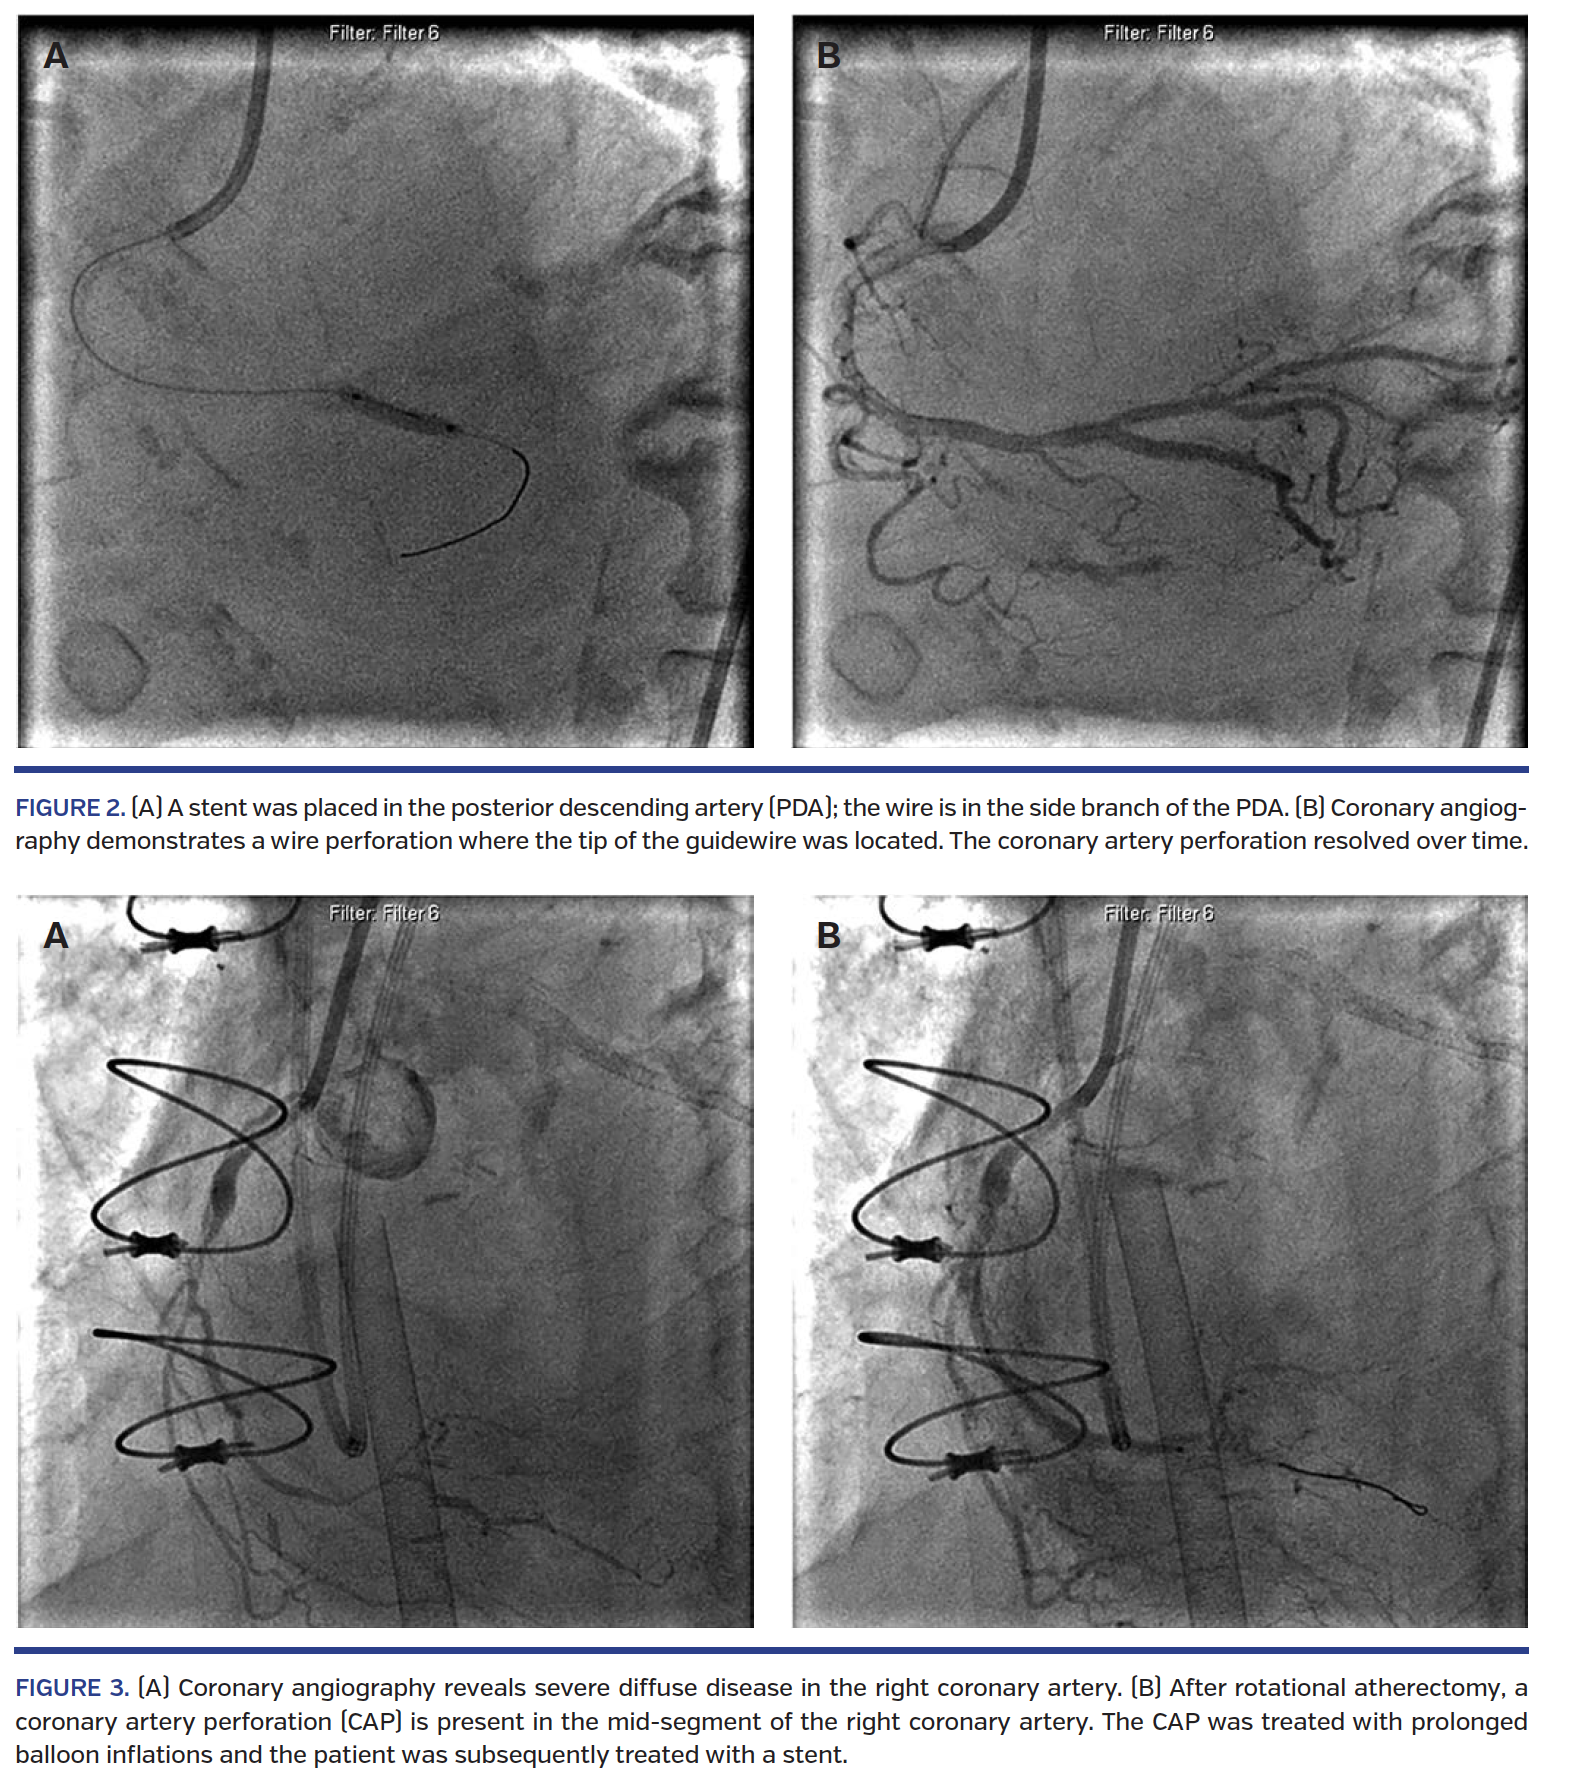

Guidewire perforation. Several studies reported guidewire-related CAP, with one study of 68 cases of CAP reporting as many as 88.9% of cases attributed to guidewires.7,12,16-19 Understandably, the higher incidence has been found in patients with complex (type C) lesions and chronic total occlusion.6,20 Injury can occur as a result of distal branch puncture or perforation at the target lesion site, especially with hydrophilic guidewires and stiff guidewires used for chronic total occlusions (Figure 2).20 One study found a significantly increased risk of delayed tamponade in guidewire-associated CAP vs CAP from other causes.20 The need for cardiac surgery is low in these patients (5.5%).

Atheroablative devices. Atheroablative devices like rotational atherectomy are used in heavily calcified vessels for plaque modification.35 In the period after rotational atherectomy devices gained popularity, the rate of CAP ranged from 0.8%-11.8%, with most studies reporting an incidence below 3%.5,9,12,15,21-29 The incidence of CAP was higher when atherectomy devices were used (2.8% vs 0.17%; P<.001; OR, 16.3; 95% CI, 7.1-37.4).14 One possible explanation for the higher risk of CAP with atheroablative devices is the effect on vascular wall integrity from debulking complex calcified lesions (Figure 3).8 Newer atheroablative devices, such as orbital atherectomy, show lower rates of CAP. In the prospective, multicenter, non-blinded ORBIT-II study involving 443 patients, 1.8% of patients suffered CAP,30 which is on the lower end of the range of CAP incidence in rotational atherectomy studies.